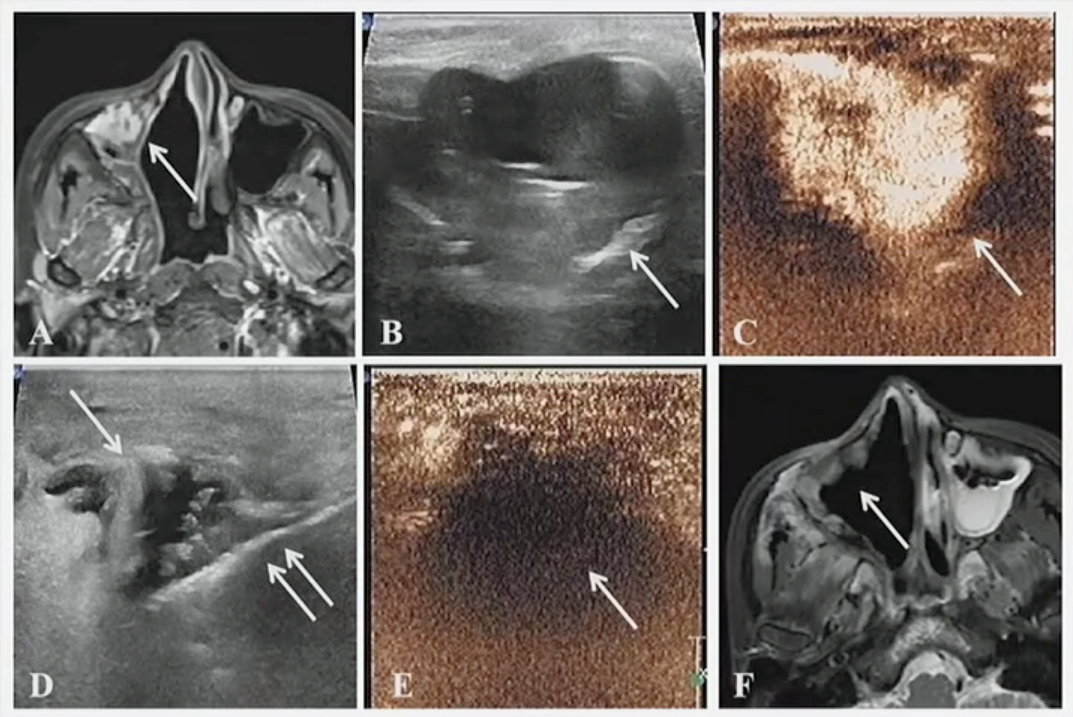

Ultrasound-guided microwave ablation (MWA) is a safe and effective procedure for treating thyroid nodules, suggest findings published September 22 in Academic Radiology.

The Eryuruk team studied MWA’s efficacy and safety for treating benign thyroid nodules. This included comparing volume reduction rates between solitary nodules and multinodular goiters, as well as assessing autonomously functioning thyroid nodules.

The single-center retrospective study included 112 patients with an average age of 58 years who were treated with MWA in 2023 and 2024. The team performed routine ultrasound and clinical evaluations at three, six, and 12 months after the procedure. It also defined technical efficacy as a 50% or more reduction in the initial nodule volume after ablation.